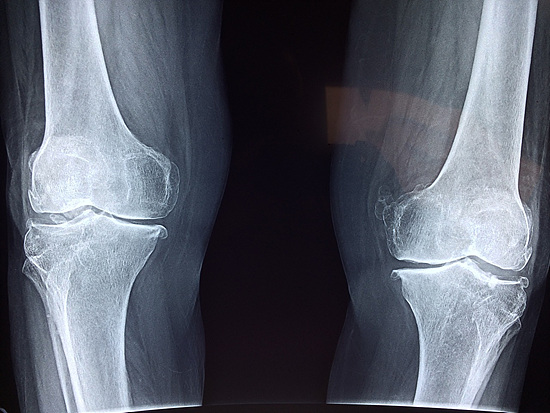

관절염: 관절염은 관절에 염증이 생기는 상태로, 이로 인해 딸깍 소리가 발생할 수 있습니다. 진단 무릎뼈 소리를 진단하려면 의사는 의학적 병력을 확인하고 신체 검사를 실시합니다.

X선 또는 MRI 검사를 사용하여 근본적인 문제를 확인하는 데 도움이 될 수 있습니다. 치료 무릎뼈 소리의 치료는 근본적인 원인에 따라 달라집니다.

- 신체 검사: 의사는 무릎을 검사하여 통증, 붓기, 압통이 있는 부위를 확인합니다.

- 엑스레이: 의사는 무릎뼈의 위치와 상태를 확인하기 위해 엑스레이를 촬영할 수 있습니다.

- MRI: 의사는 무릎뼈의 연골과 인대 상태를 확인하기 위해 MRI를 실시할 수 있습니다.